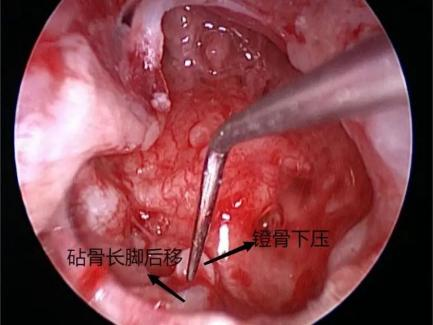

耳内镜下初步对异物情况进行判断,不可能直接取出。遂启动第二方案,微创行耳内切口,扩大术腔,磨除外耳道骨质,扩大外耳道。因石头棱角较多,主刀医生边松动石头边磨除棱角处骨质,小心旋转角度,向外用力终于取出约6.6mm×4.3mm的异物。

术后患儿安全返回病房,予以加强抗炎治疗,患儿无右耳痛、出血,眩晕逐渐减轻。待鼓室及外耳道黏膜恢复正常,再择日行鼓膜修补或同期行人工听骨听力重建术。病情稳定后,患儿于术后第4天出院。